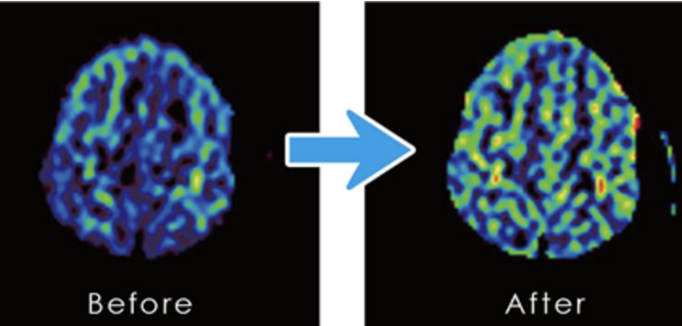

実験者6名をMRIにて脳血流を測定し、その後10分間脳大成理論のマインドテクノロジーを実践し再度MRIにて脳血流を測定しました。

その内3人の方の脳大成理論におけるマインドテクノロジー前後のCBF(脳血流)画像。

左が何もしない状態でMRI測定した写真(ビフォア)で、右が10分間マインドテクノロジーを実行してからMRI測定した写真(アフター)となります。

頭頂葉と大脳皮質に血流増加が見られる。

以上の結果から、脳大成理論のマインドテクノロジーを実践することにより、脳血流が向上することが明らかになりました。講座・研修での体感・体験実験(ワークス)で実感できる変化や、脳大成理論に取り組んだ後に現実に表れた変化や成果のみならず、前に示したように確実に脳に変化が現れることが実証できました。